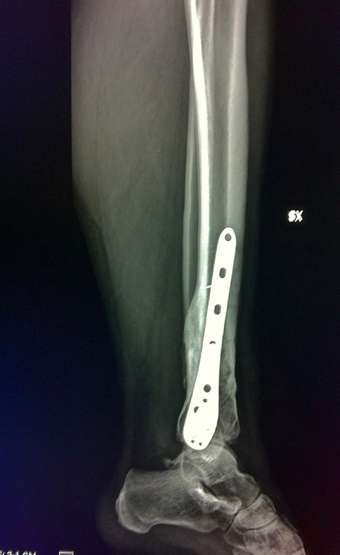

Seconda operazione: rimozione placca rotta e "montaggio" nuova placca:

[​IMG]

Nuova placca

La prima operazione è stata nel 04/2010 (prima piastra)

La seconda nel 10/2010 (sostituzione piastra)

La terza nel 04/2012 (rimozione seconda piastra)